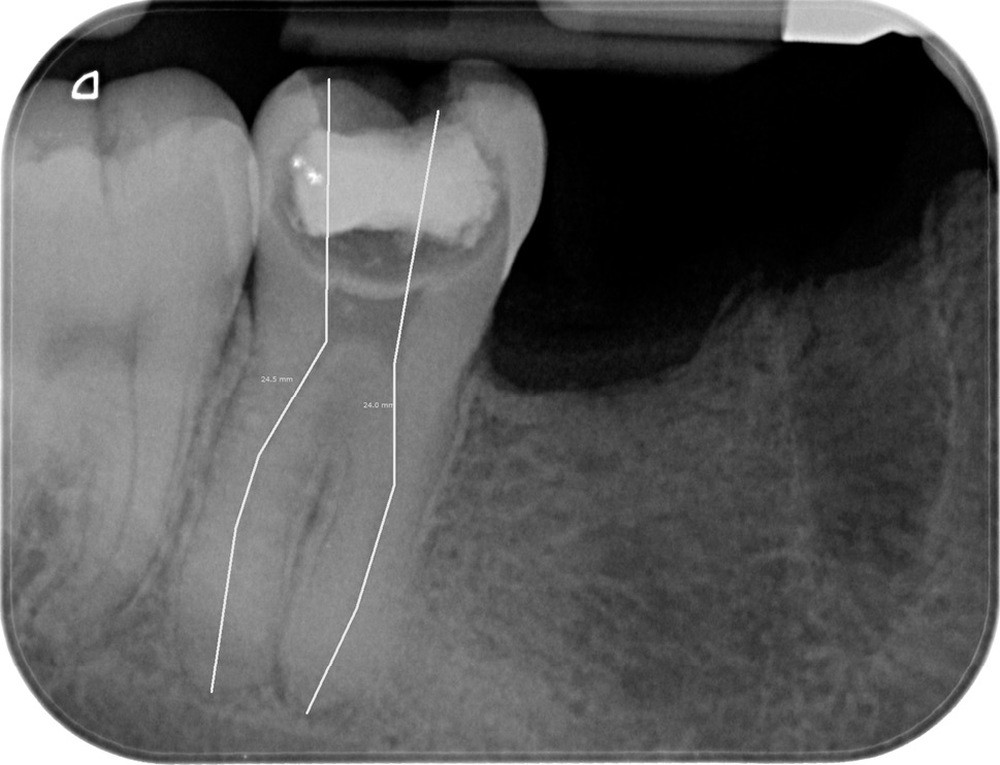

1.Radiographie rétroalvéolaire préopératoire montrant une lésion carieuse occlusale extrêmement volumineuse sur 46.